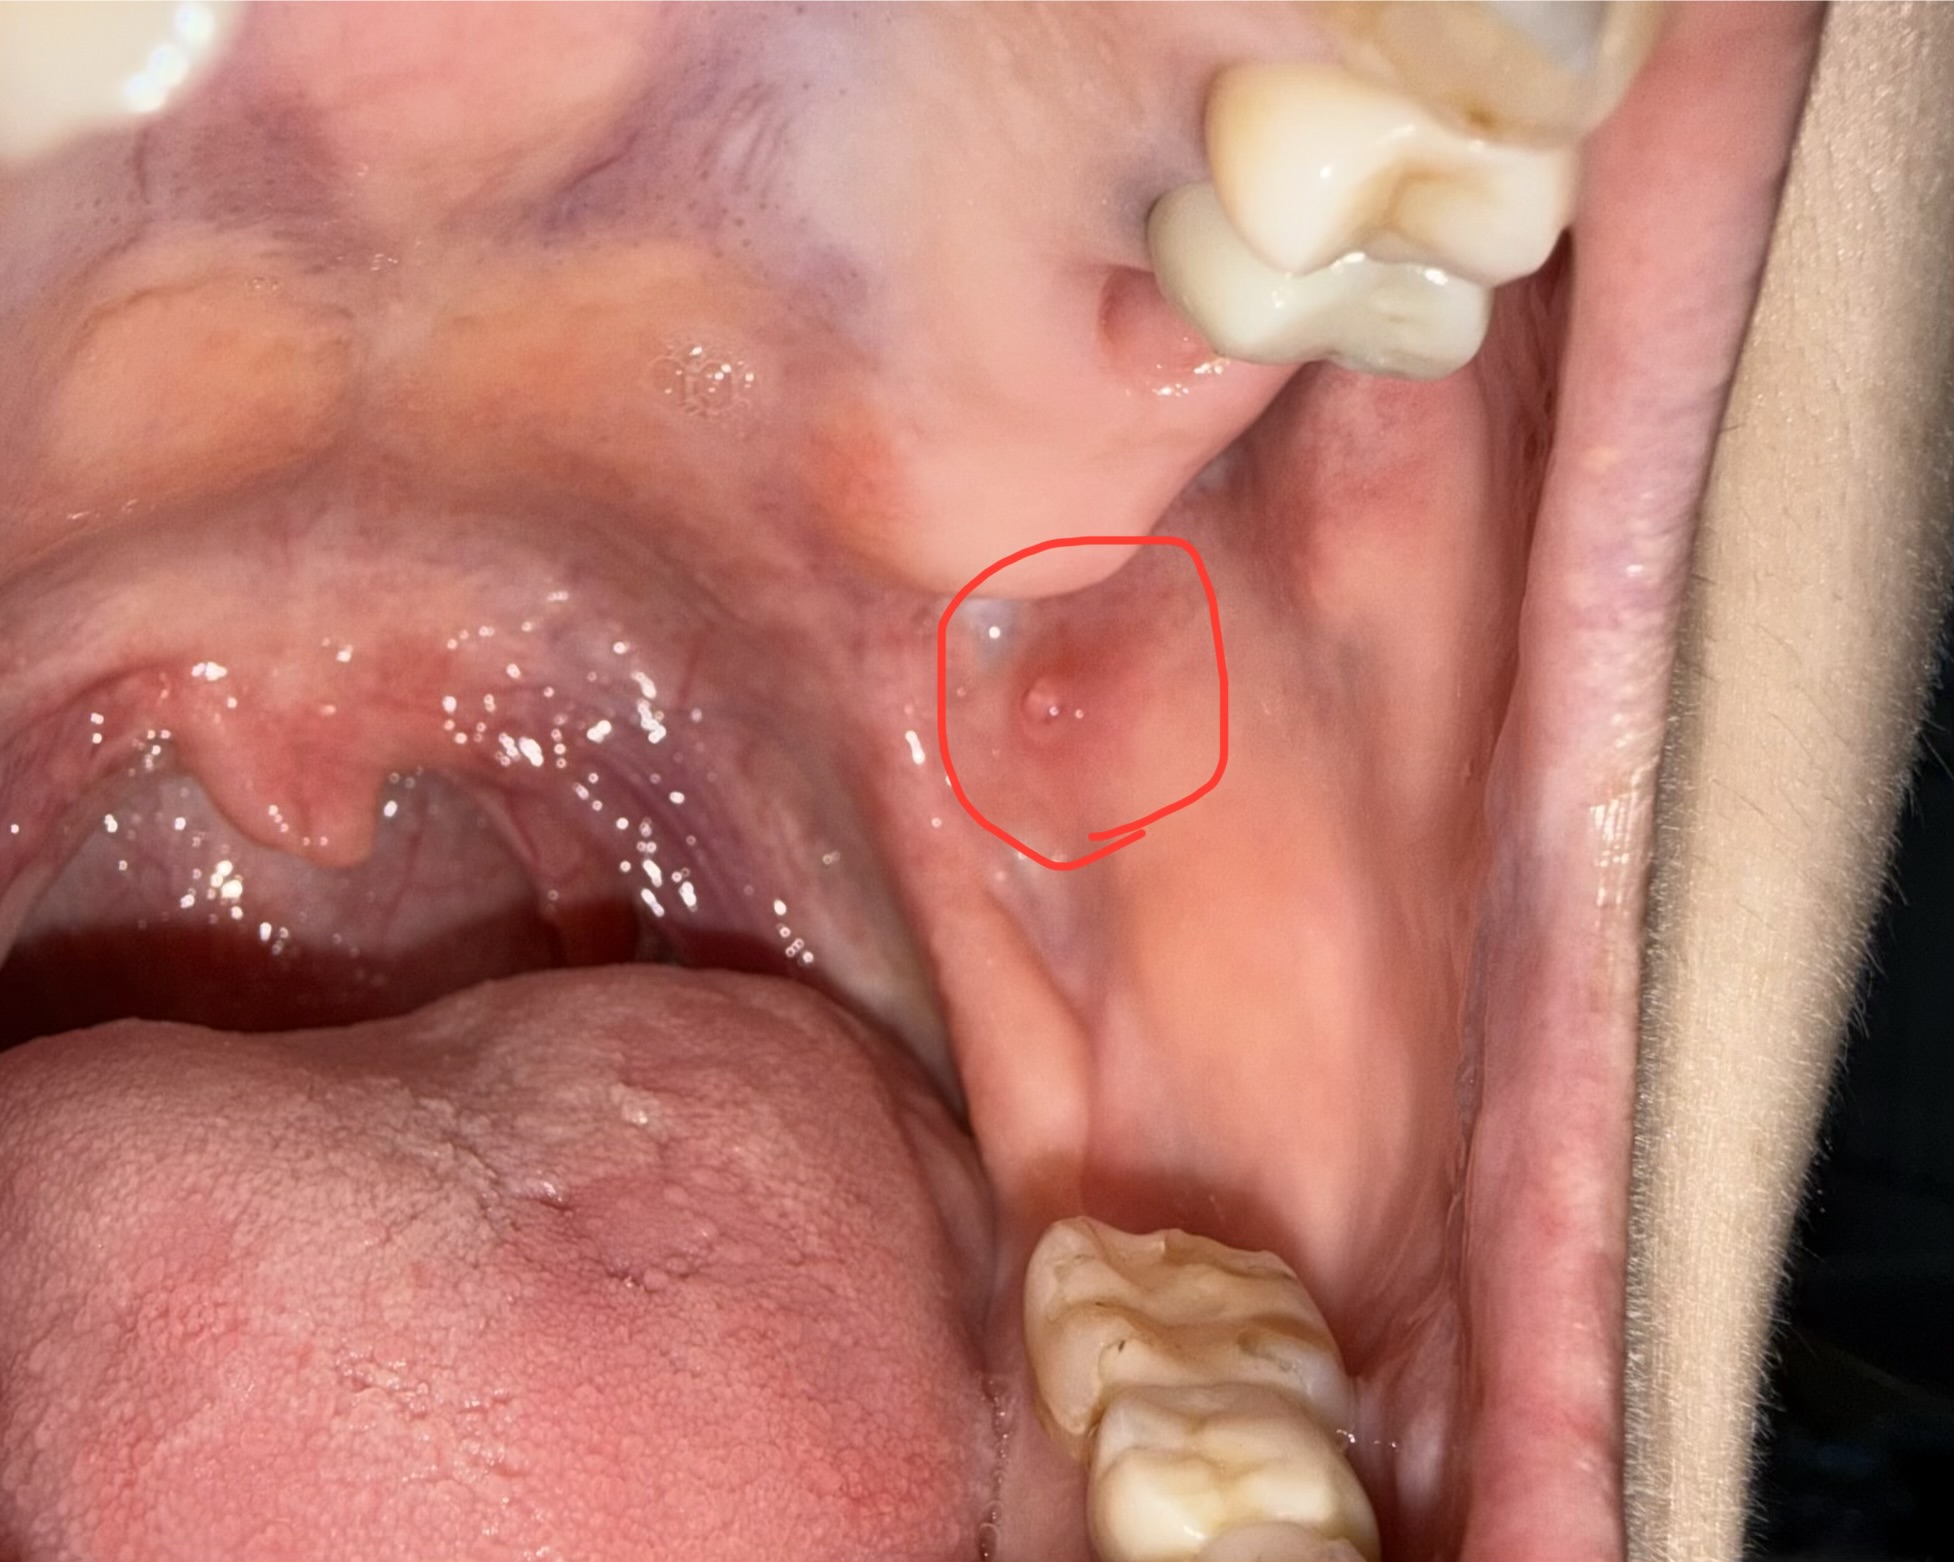

口の中に透明なできものがあります。唾液腺でしょうか?